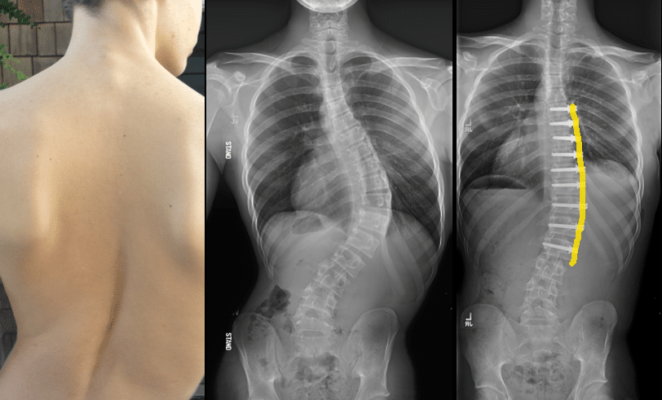

ASC側湾症手術前側湾症矯正の利点と回復プロセス

ASC側湾症手術の効果と回復過程をご覧ください。前側弯症の矯正について学ぶ [...]...